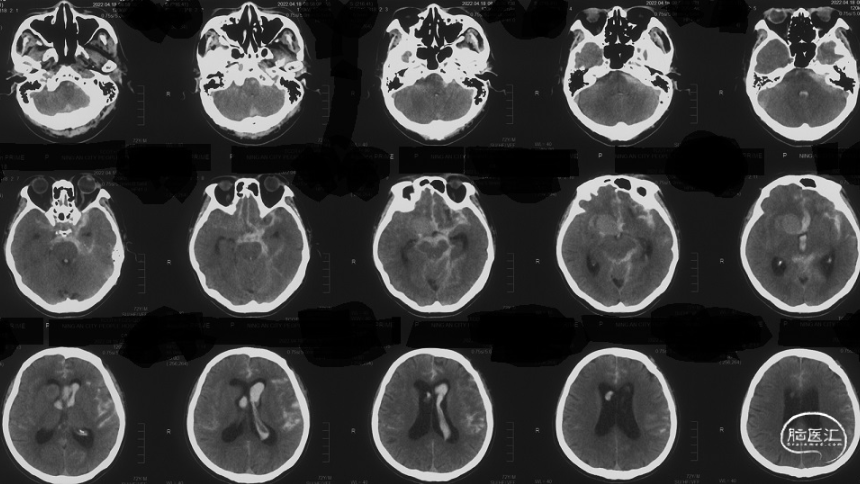

“又是它,大大的瘤,宽宽的颈,实则像个水母”。

标准侧位发现,这个位置有些残留,角度还是比较刁的,不太好到位。虽然有这么一点小遗憾。但是从患者是未破裂动脉瘤,及减少患者风险为第一位的角度上看,还是可以考虑一下。因此毅然决定收手。术后患者安好。

静下来想想,有的时候我们追求完美,让手术和患者得到最大的受益无可厚非。但是有的时候能及时收手,减少患者由于增加操作而带来的风险,未尝不是一种正确的选择。仅为个人观点,与诸君分享。同时感谢各位关注。